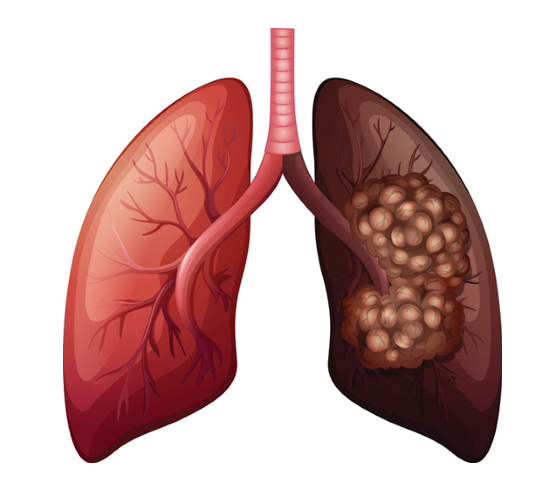

폐암은 흡연자의 경우 비흡연자보다 폐암이 발생할 가능성이 훨씬 높으며, 폐암이 무서운 이유는 사망률이 85퍼센트가 확진 후 5년 안에 사망할 정도로 높기 때문입니다. 폐암은 한국에서 두 번째로 흔한 암으로 아주 무서운 질환입니다. 말 그대로 폐의 악성종양을 뜻하고 장기간 흡연하는 흡연자에게 특히나 발병율이 높으며 최근에도 여러 환경적 요인에 의해 발병하며 있습니다.

폐암 원인에는 여러가지 원인이 있습니다. 유전적 요인, 환경적 요인 등이 있고 암은 먼저적으로 가족력이 있으면 남들보다 이른 나이부터 계속해서 검사를 받고 관리가 필요하며 갖 환경적 요인으로 인해서 흡연을 하지 않는 여성에게도 폐암이 풍부하게 나타나고 있는 점을 고려할 때 주방에서 가스레인지로 조리시 나오는 갖가지 발암물질 등으때문에 폐암이 병이 발생율이 높아진 것으로 알려져 있습니다.유전적, 환경적 요인 이외에 폐암 대표 원인이 되는 흡연은 직간접적으로 영향이 강해서 폐암 원인과 떼어놓을 수 없는데 폐암을 판정 받는 환자 70퍼센트는 흡연에 의한 것으로 체크되고 있어 간접 흡연으로 인한 피해와 본인 건강을 위해서도 금연을 하는 것이 중요합니다.